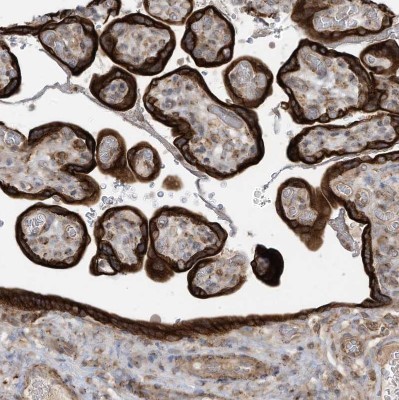

- Immunohistochemistry-Paraffin: cGAS Antibody [NBP2-55374] - Staining of human placenta shows strong cytoplasmic positivity in trophoblastic cells.